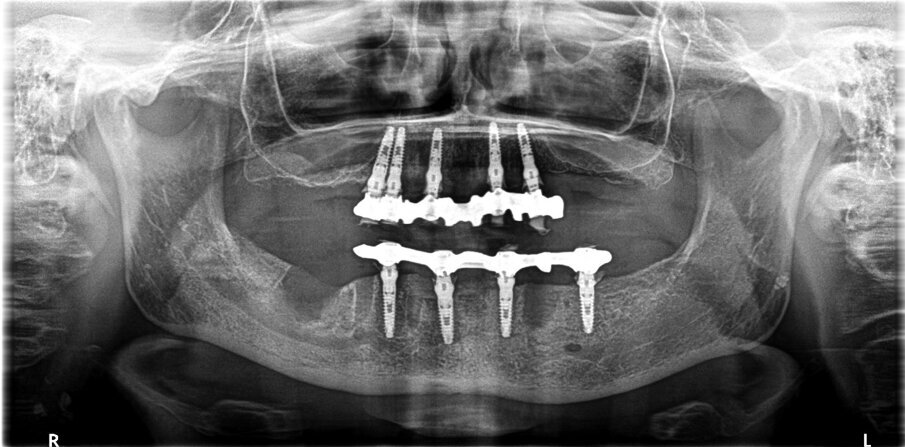

Paziente donna di ottant’anni, presenta uno stato di salute ottimale, non assume farmaci. Dal punto di vista odontoiatrico chiede una riabilitazione delle due arcate con dei denti fissi perché le attuali protesi removibili con ganci le stanno creando ormai da troppi anni un grande disagio. Come dalla ortopantomografia possiamo evidenziare uno stato ormai precario degli elementi rimasti (Figg. 1-3).

Come primo passo per questa riabilitazione è necessario prendere due impronte con scanner 3D, naturalmente senza le protesi per poter eseguire due tamponi occlusali. Il secondo passo è quello di far preparare al laboratorio due dime radiologiche con polvere di bario; questo passo è estremamente importante perché, se viene eseguita una radiografia 3D con le dime malposizionate, tutto il lavoro che seguirà sarà un errore continuo. Tra queste dime radiologiche è stato posizionato uno Stent radiografico che permetterà, una volta eseguita la TAC, di eseguire un Mach di riconoscimento dei due modelli tramite software di pianificazione implantare. Dalla diagnosi virtuale è stato riscontrato che nella parte superiore era presente un osso che va da una densità D2 nella parte anteriore e tra il D2 e D3 nella parte posteriore, mentre l’inferiore presenta un osso con densità D2 su gran parte della superficie disponibile per ospitare gli impianti. Una volta posizionati virtualmente gli impianti è stato inviato al laboratorio il file STL che permetterà di costruire una protesi virtuale e di conseguenza le dime chirurgiche (Figg. 4, 5).